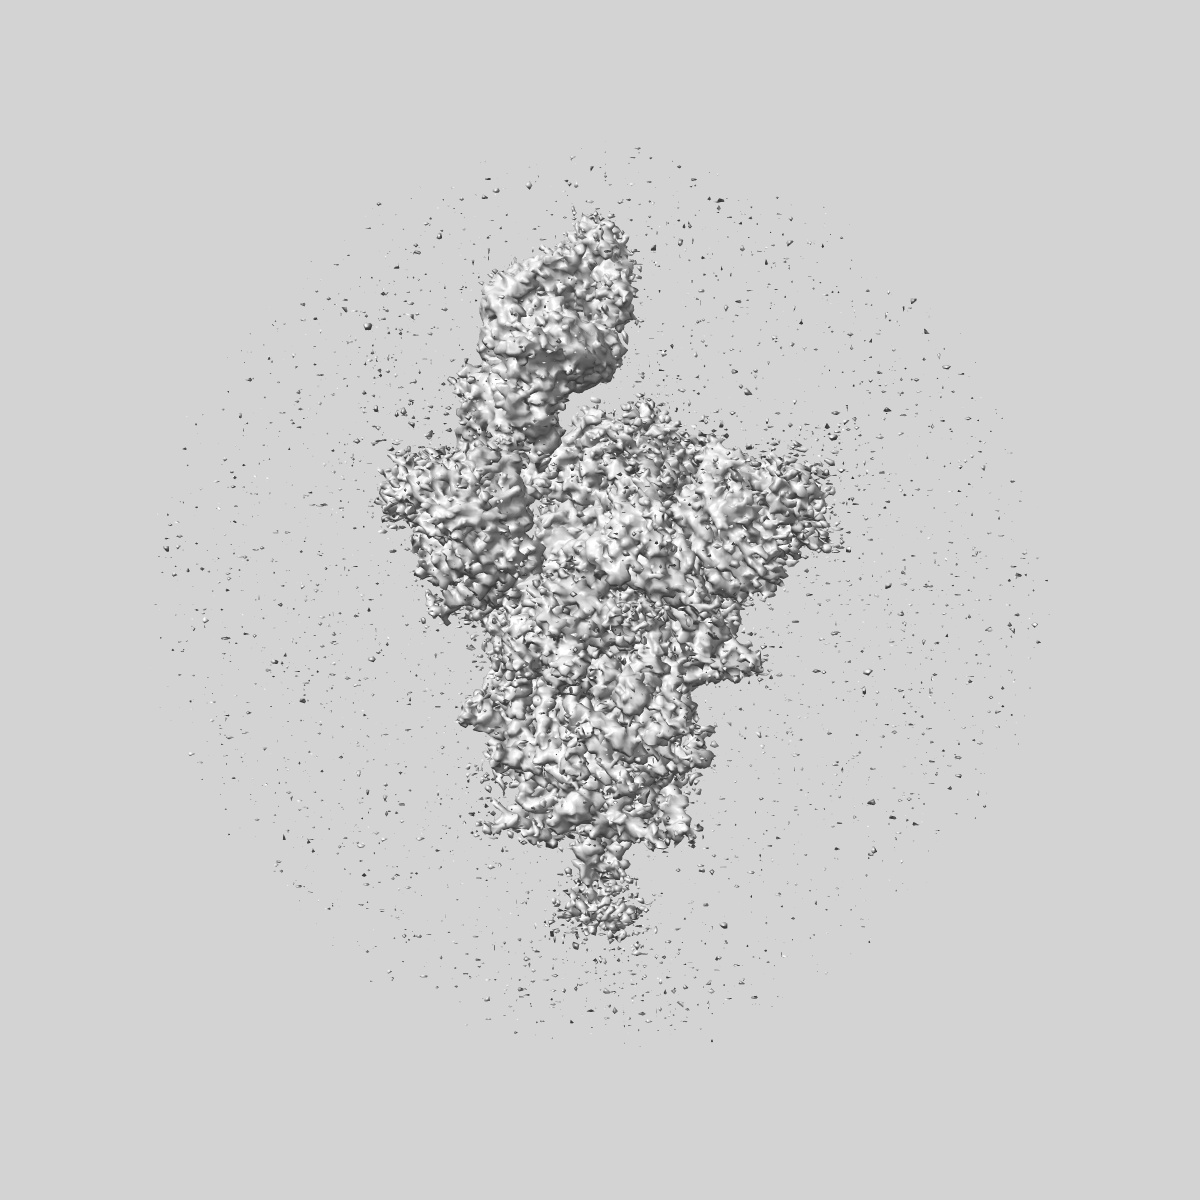

SARS-CoV-2 Wuhan Spike ectodomain in complex with human polyclonal antibody ModWu-RBD2 (mRNA-1273 vaccine)

Sample: SARS-CoV-2 Wuhan spike ectodomain in complex with human polyclonal antibody ModWu-RBD2

Single-particle3.2 Å